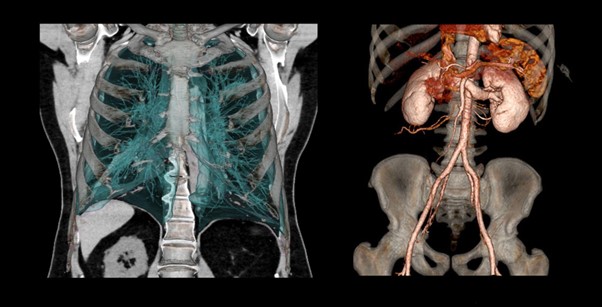

Khả năng chụp toàn bộ cơ thể phối hợp với công nghệ dựng hình 3D hiện đại giúp khảo sát tổn thương của nhiều cơ quan

Ảnh dựng 3D bằng máy CT 160 lát Aquilion Prime SP